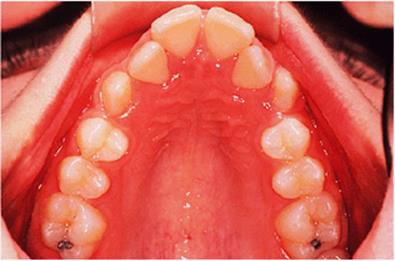

Where the premolars erupt before the pubertal growth spurt takes place, the sequence of treatment can be reversed. The crowding is relieved by extracting premolar teeth, and then the arches are aligned using fixed or removable appliances, or a combination of the two, but making no attempt to correct the incisor or molar relationships (Fig. 18.2). The functional appliance is fitted when the arches have been aligned, and some designs can be made to fit over a fixed appliance. It should be worn until the growth spurt is complete, and can serve as a retainer after the brackets have been removed.

Where the upper molars are clasped, there can be no spontaneous expansion of the upper arch while the activator is being worn. Therefore it is necessary to fit an expansion appliance first, such as that shown in Fig. 18.8. This gives the patient an easy introduction to appliance wear, and it may also include springs to improve the alignment of the upper incisors. In cases where a fixed appliance has been used to align the arches before fitting the functional appliance, the medium opening activator design can be modified to fit around fixed attachments (Fig. 18.2).

Fig. 18.8. Expansion appliance fitted prior to the functional appliance.